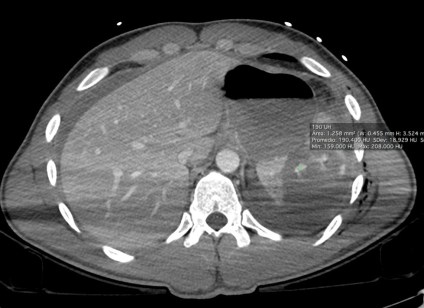

Varón jóven que acude a urgencias tras accidente de moto. Presenta dolor acusado en flanco izquierdo.

TA: 80 / 50 ; FC 110 lpm; Sat O2 93%.

Analítica: Discreta anemia.

Ante estos hallazgos, estamos ante un traumatismo esplénico grado III. Con la edad del paciente y los indicios de inestabilidad hemodinámica, se decidió tratamiento mediante embolización arterial.

Debe hacerse en fase dual, la fase portal detecta mejor el sangrado activo y las lesiones parenquimatosas como contusiones o laceraciones, mientras que la fase arterial es útil para diagnosticar lesiones vasculares como un seudoaneurisma o fístulas.

- Hemorragía activa: áreas de alta densidad (80 – 95 UH) por extravasación de material de contraste que aumenta con el tiempo. Es un indicador de fallo del tratamiento conservador.

- Pseudoaneurismas y fístulas AV: tienen similar apariencia a la de una hemorragia, pero incrementan de tamaño con el tiempo y se lavan en fase portal.